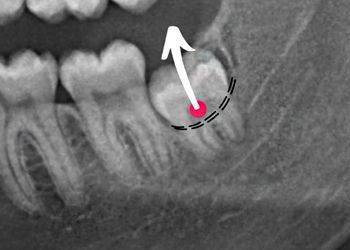

TROUGHING & BONE REMOVAL

Get clear, practical answers on when to trough bone, how much to remove, and which bur to choose—everything I wish I knew when I started.